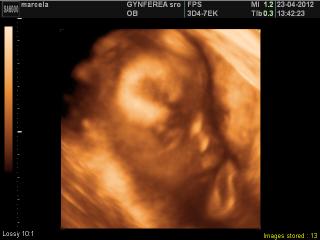

@miskachrumka ahoj včera som nemala čas ale dnes som tu fotku sem už šupla 🙂 tak už vieš ským si píšeš 🙂

@marcela2003 booze je rozkosnaaaaa

@marcela2003 kraaasna 🙂

@marcela2003 kraaasnu tvaricku ma, ako babika